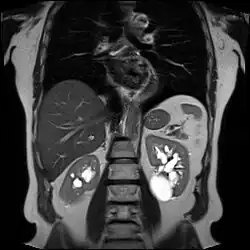

Advanced polycystic kidney disease with multiple cysts.[13] -

Numerous renal cysts are seen in the cystic kidney diseases, which include polycystic kidney disease and medullary sponge kidney.